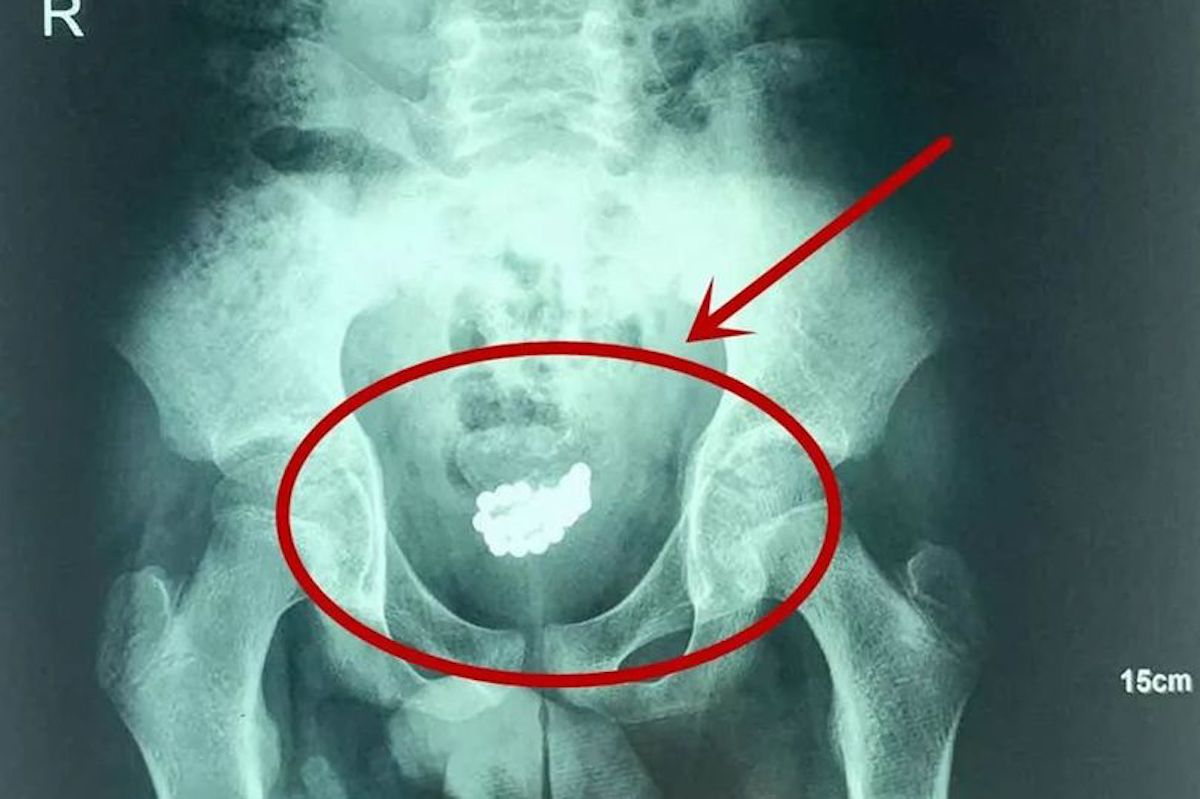

On dit souvent que l'adolescence correspond à l'âge bête... Cette histoire qui nous vient du sud-est de la Chine va encore une fois le prouver. En effet, un adolescent chinois âgé de 13 ans s'est fait retirer de son pénis 29 billes aimantées par une équipe de chirurgiens de l'hôpital pour enfant de Xi'an, dans la province du Shaanxi.

Cela faisait trois mois que l'adolescent vivait avec ces billes magnétiques coincées dans son pénis après les avoir insérées dans son urètre uniquement "par curiosité" comme l'explique l'urologue qui l'a pris en charge. Trop gêné pour aller consulter, il a préféré vivre avec malgré de fortes douleurs abdominales.

Quand les parents du jeune garçon ont découvert ce qu'avait fait leur fils, c'est à ce moment là qu'ils ont décidé de le transporter à l'hôpital. Les médecins ont alors découvert que les billes commençaient à former un amas près de la vessie du jeune garçon.